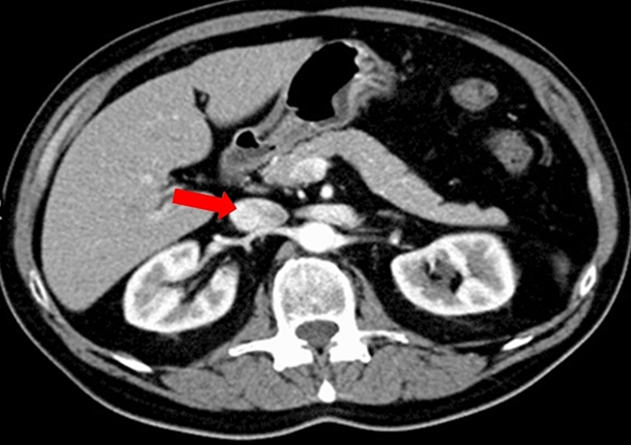

Hombre de 52 años, consulta a su servicio de urgencias por un dolor abdominal agudo no especificado. Se decide realizar una tomografía abdominal con contraste intravenoso, la cual es normal. Según el corte axial mostrado a continuación (por favor ubique bien el lado y que es anterior/posterior):

¿Cuál de las siguientes opciones describe mejor la estructura señalada en rojo?